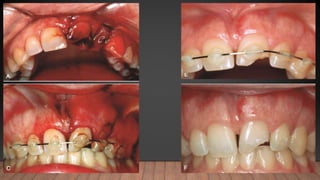

CROWN FRACTURE

• Depth of involved tissue

• Enamel vs. Dentin involvement vs. Pulpal involvement

• Periodic Follow-up

CROWN-ROOT

FRACTURE.

• Location of the fracture and local anatomic variance.

• If the fracture does not descend too far apically, restorable and the pulp has not been

exposed.

• Orthodontic extrusion, Periodontal procedures, endodontic treatment